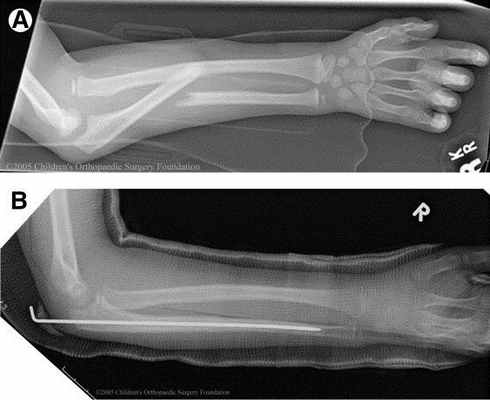

В некоторых случаях остеосинтез производят спицами или спонгиозным винтом.

Аппарат внешней фиксации применяют при открытых переломах костей предплечья, а также при переломах дистального отдела предплечья.

При диафизарных переломах предплечья внешний фиксатор применяют как временное устройство до заживления раны мягких тканей, после чего производят внутренний остеосинтез. При закрытом остеосинтезе в исключительных случаях для анатомической репозиции можно выполнить малый разрез над линией перелома.

Вешняя фиксация при переломе лучевой кости в типичном месте.